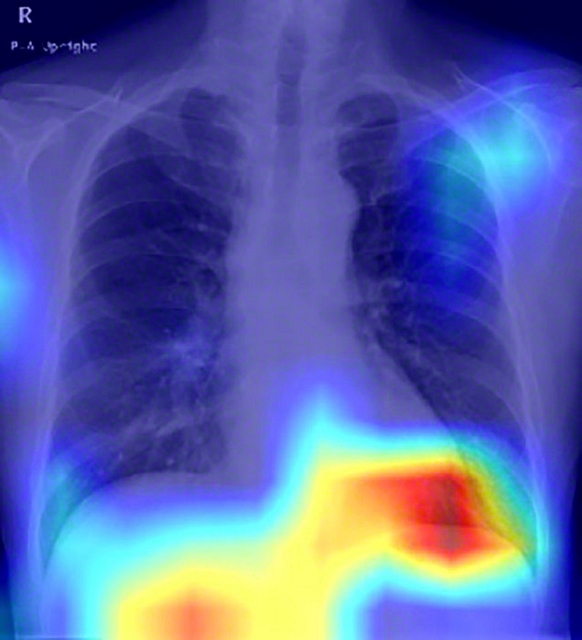

脂肪肝患者の胸部エックス線画像。AIモデルが脂肪肝の判別のためにより注目した部位が濃い赤で表示されている(大阪公立大学提供)

健康診断で行われる胸部エックス線で、脂肪肝を判別できるAIの研究について紹介します。また、働く人の3人に1人が腰痛などの不調があるという調査や、高齢者のうつと…